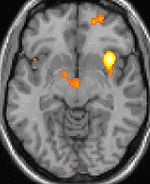

The brain in itself is not sensitive to pain, because it lacks nociceptors. Several areas of the head can hurt, including a network of nerves which extend over the scalp and certain nerves in the face, mouth, and throat. The meninges and the blood vessels do have pain perception. Headaches often result from traction to or irritation of the meninges and blood vessels. The membrane surrounding the brain and spinal cord, called the dura mater, is innervated with nociceptors. Stimulation of these dural nociceptors is thought to be involved in producing headaches. Similarly the muscles of the head may be sensitive to pain.

The most common type of vascular headache is migraine. Migraine headaches are usually characterized by severe pain on one or both sides of the head, an upset stomach, and, for some people, disturbed vision. It is more common in women. While vascular changes are evident during a migraine, the cause of the headache is neurologic, not vascular. After migraine, the most common type of vascular headache is the "toxic" headache produced by fever.